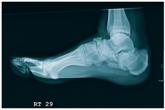

A 51-year-old man is brought to your facility for evaluation of right foot pain after sustaining a fall. He was working on top of his house when he lo...